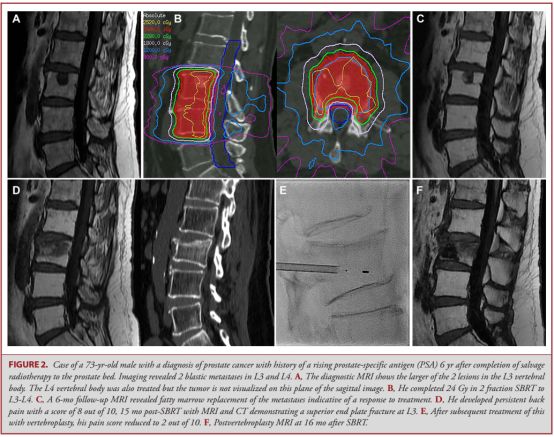

10.脊柱立体定向放射治疗后椎体压缩性骨折:病理生理学和危险因素

Vertebral Compression Fracture After Spine Stereotactic Body Radiation Therapy: A Review of the Pathophysiology and Risk Factors.

PMID: 29048517 DOI: 10.1093/neuros/nyx493

椎体压缩性骨折(VCF)是脊柱立体定向放射治疗(SBRT)后观察到的一种相对常见的并发症。该研究总结了已发表的多项研究的数据,评价脊柱SBRT后VCF的风险和预测因素。

在11项纳入分析的研究中,共有2911例符合条件的患者,在脊髓节段治疗后的VCF发生率为13.9%。多变量分析中最常见到的危险因素是:融合性病变;立体定向体放射治疗前的椎体压缩性骨折发生;立体定向放射剂量增高后的发生差异;脊柱畸形;年龄较大以及超过40%-50%的椎体涉及肿瘤。

椎体压缩性骨折(VCF)是脊柱立体定向放射治疗(SBRT)后的常见不良反应,基于以上发现来确定危险因素来指导挑选出高风险患者,对于患者是否放射干预做出选择具有重要意义。

![]()